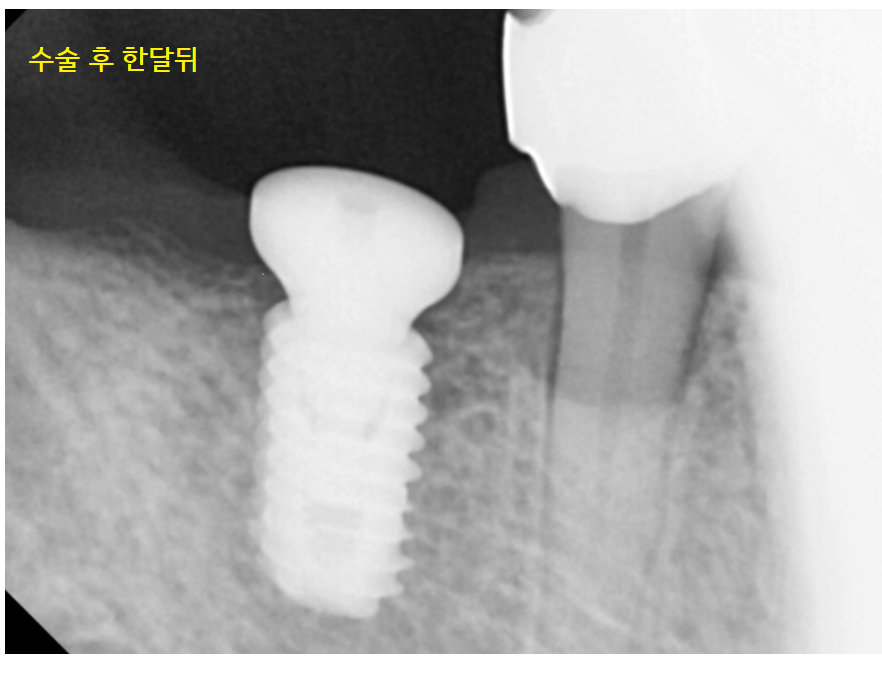

21.02.04

고덕역 임플란트 수술 후 한 달 뒤 사진입니다.

아래 임플란트의 경우 평균적으로 3개월 정도의

임플란트와 내 뼈가 붙는 시간이 필요합니다.

아직은 임플란트 주변으로

부분 부분 어둡게 보이죠~

그렇다면 3개월 뒤의 사진을 보겠습니다.